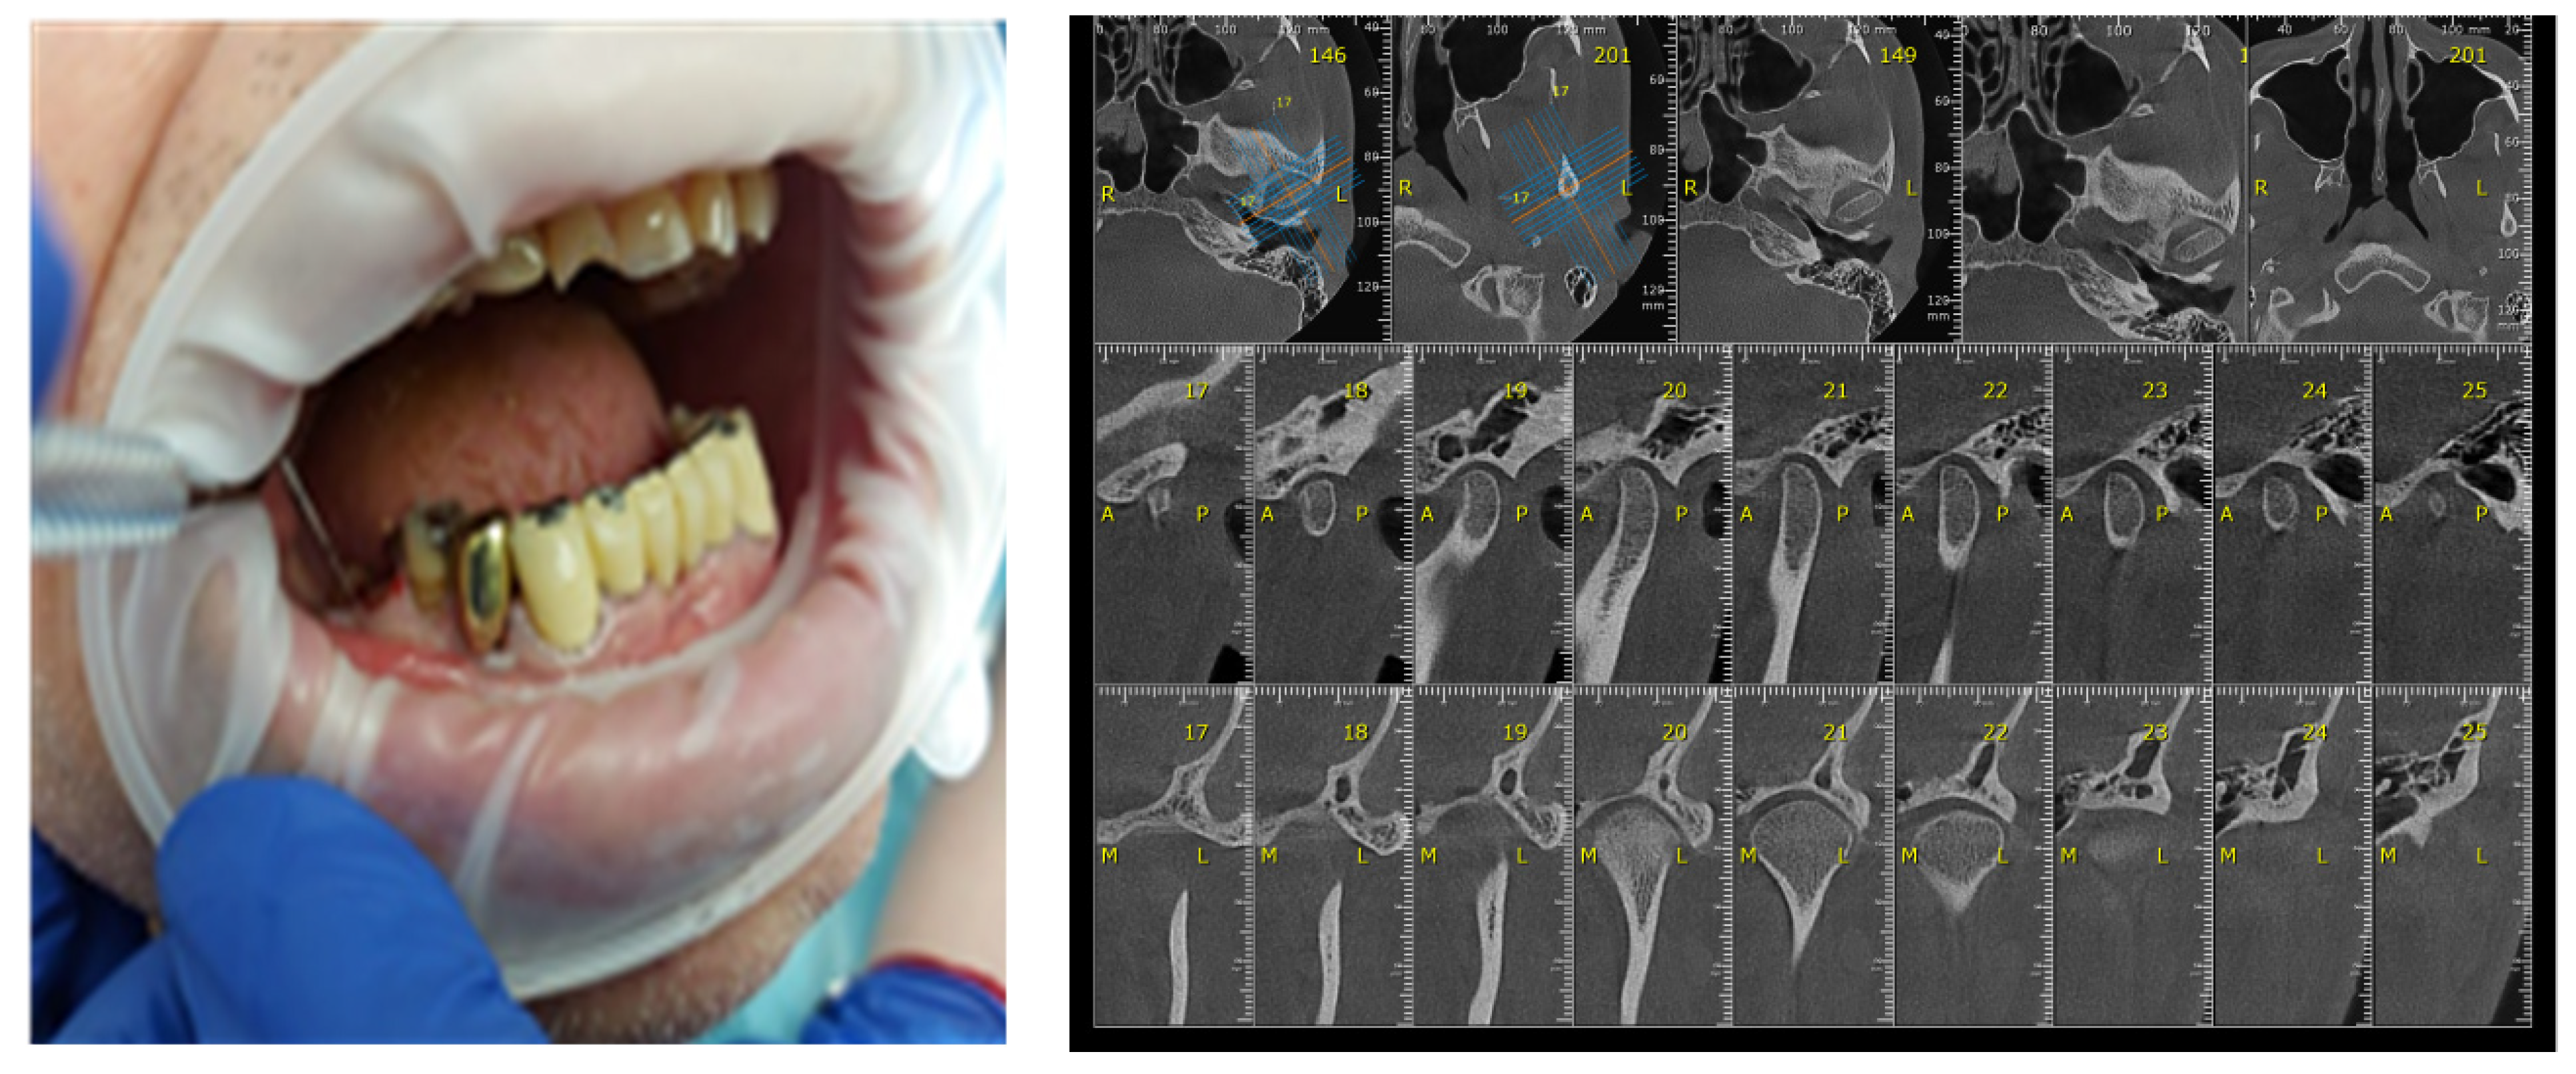

3. Materials and Methods